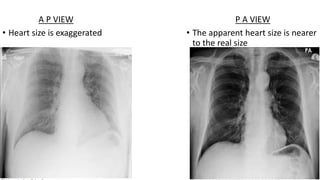

This document discusses key aspects of thorax radiology including positioning for PA and AP views, assessing heart size, visibility of anatomical structures like the scapulae, lungs zones, and measurements like cardiothoracic ratio. It provides guidance on evaluating rotation, inspiration, and penetration on chest x-rays as well as identifying structures like the lobe of azygos vein and aortic knuckle.